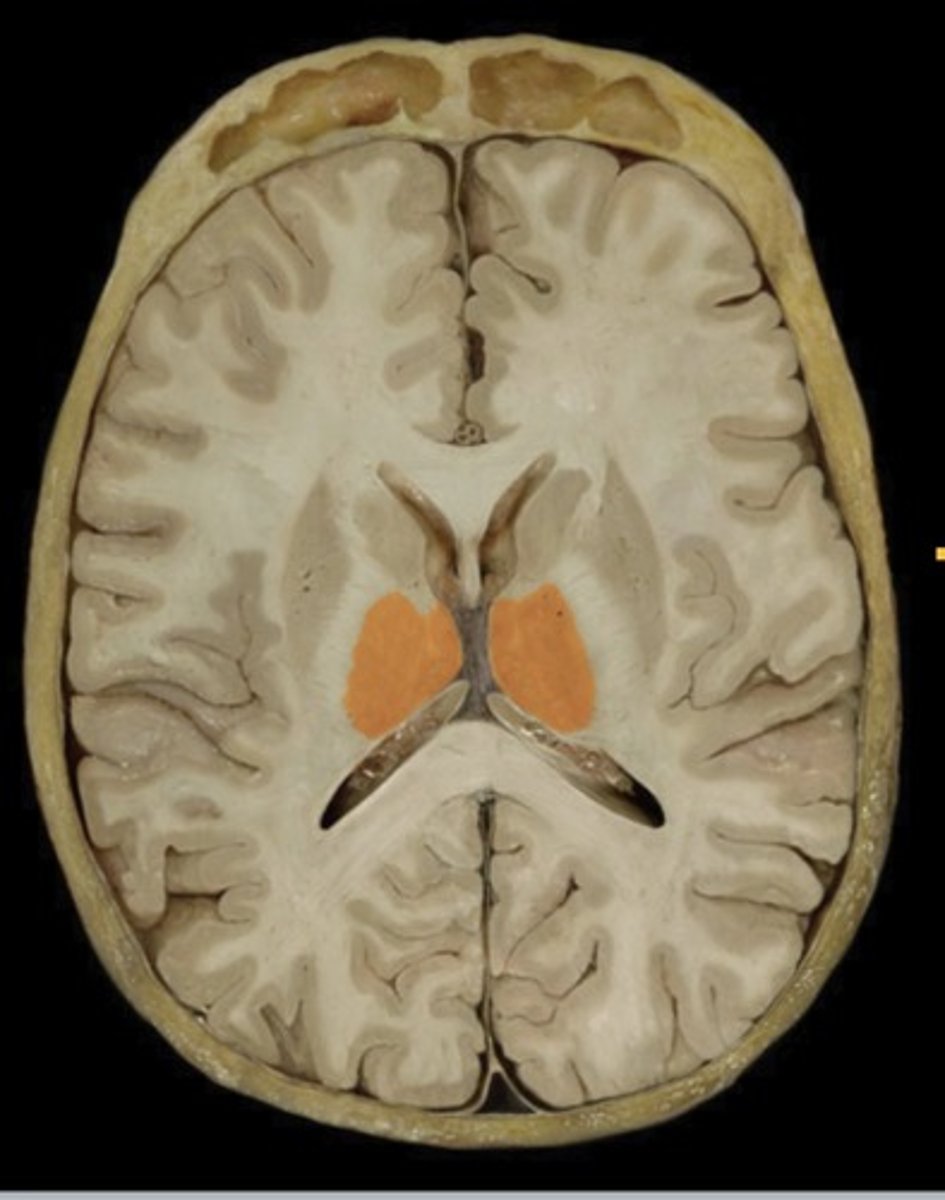

Basal Nuclei

Name this structure

Thalamus (transverse section)

Name this structure